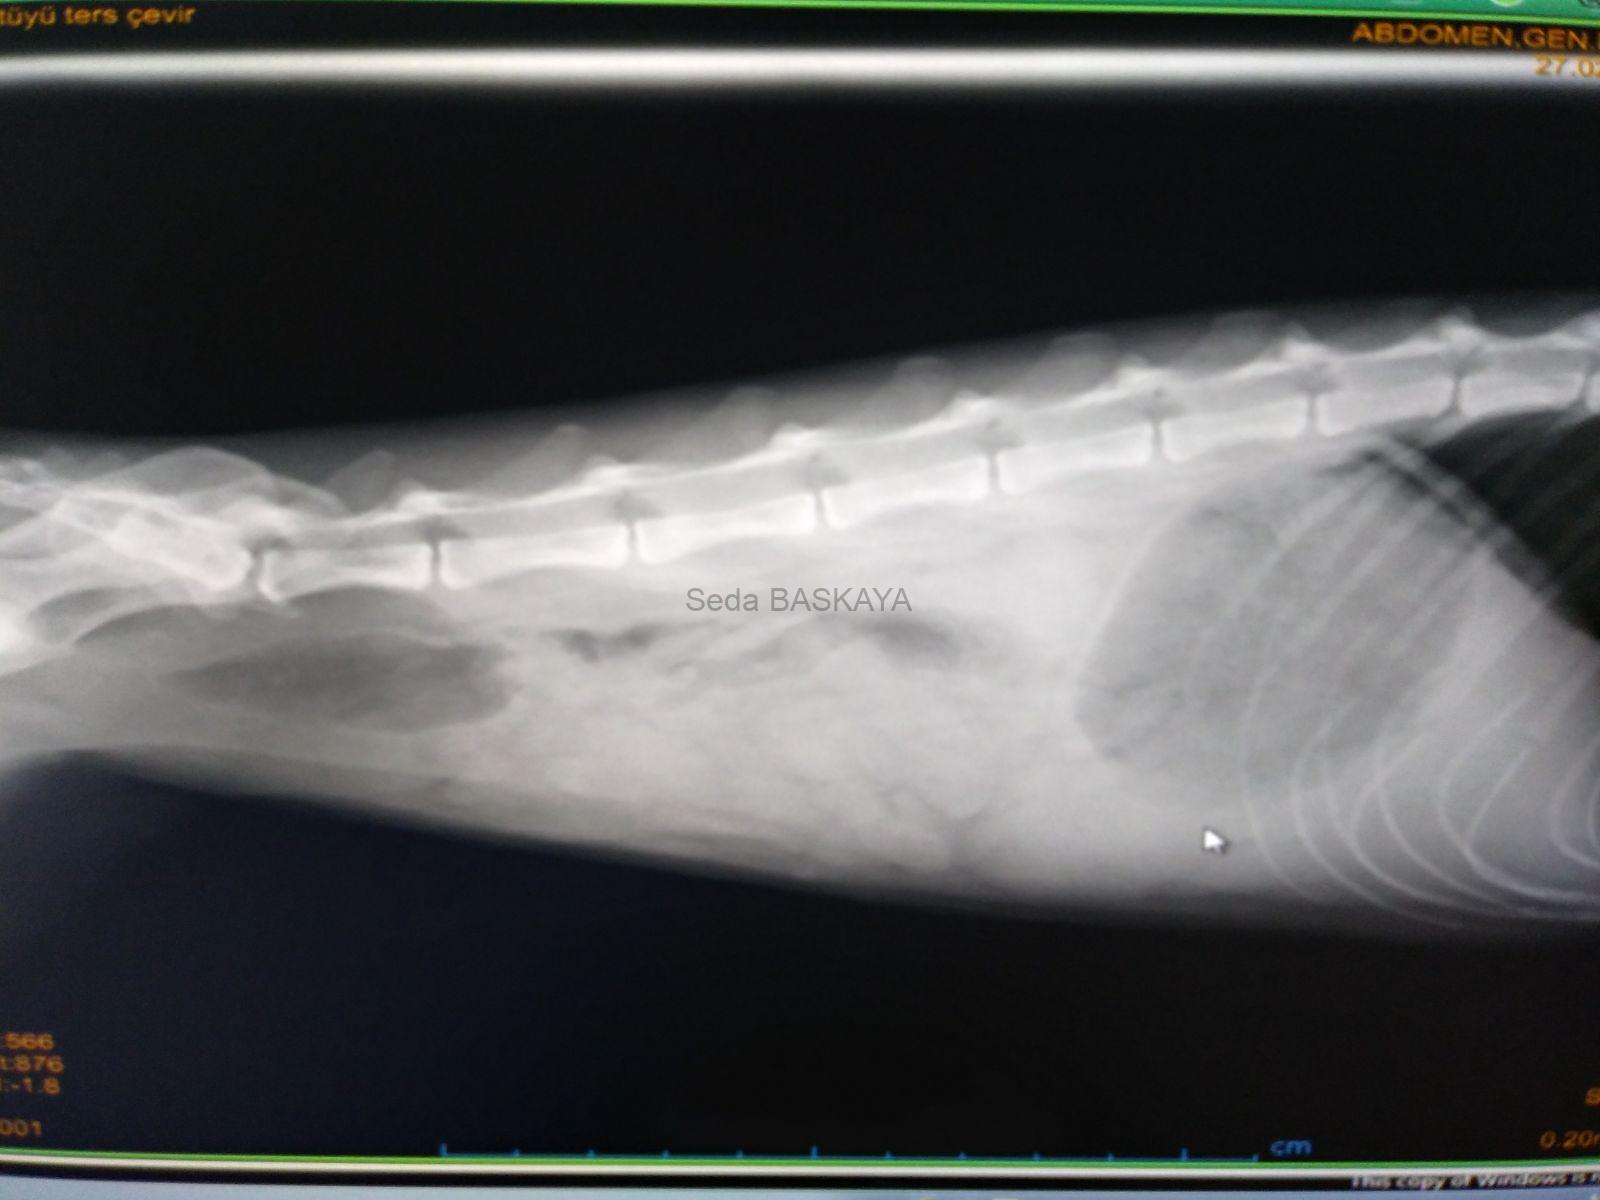

Emergency operation Gastric Volvulus Dilatation

In our surgery lesson: “You may see this case once in our professional life.” started by saying, Surgery Professor Kemal. After graduation; The first clinical…